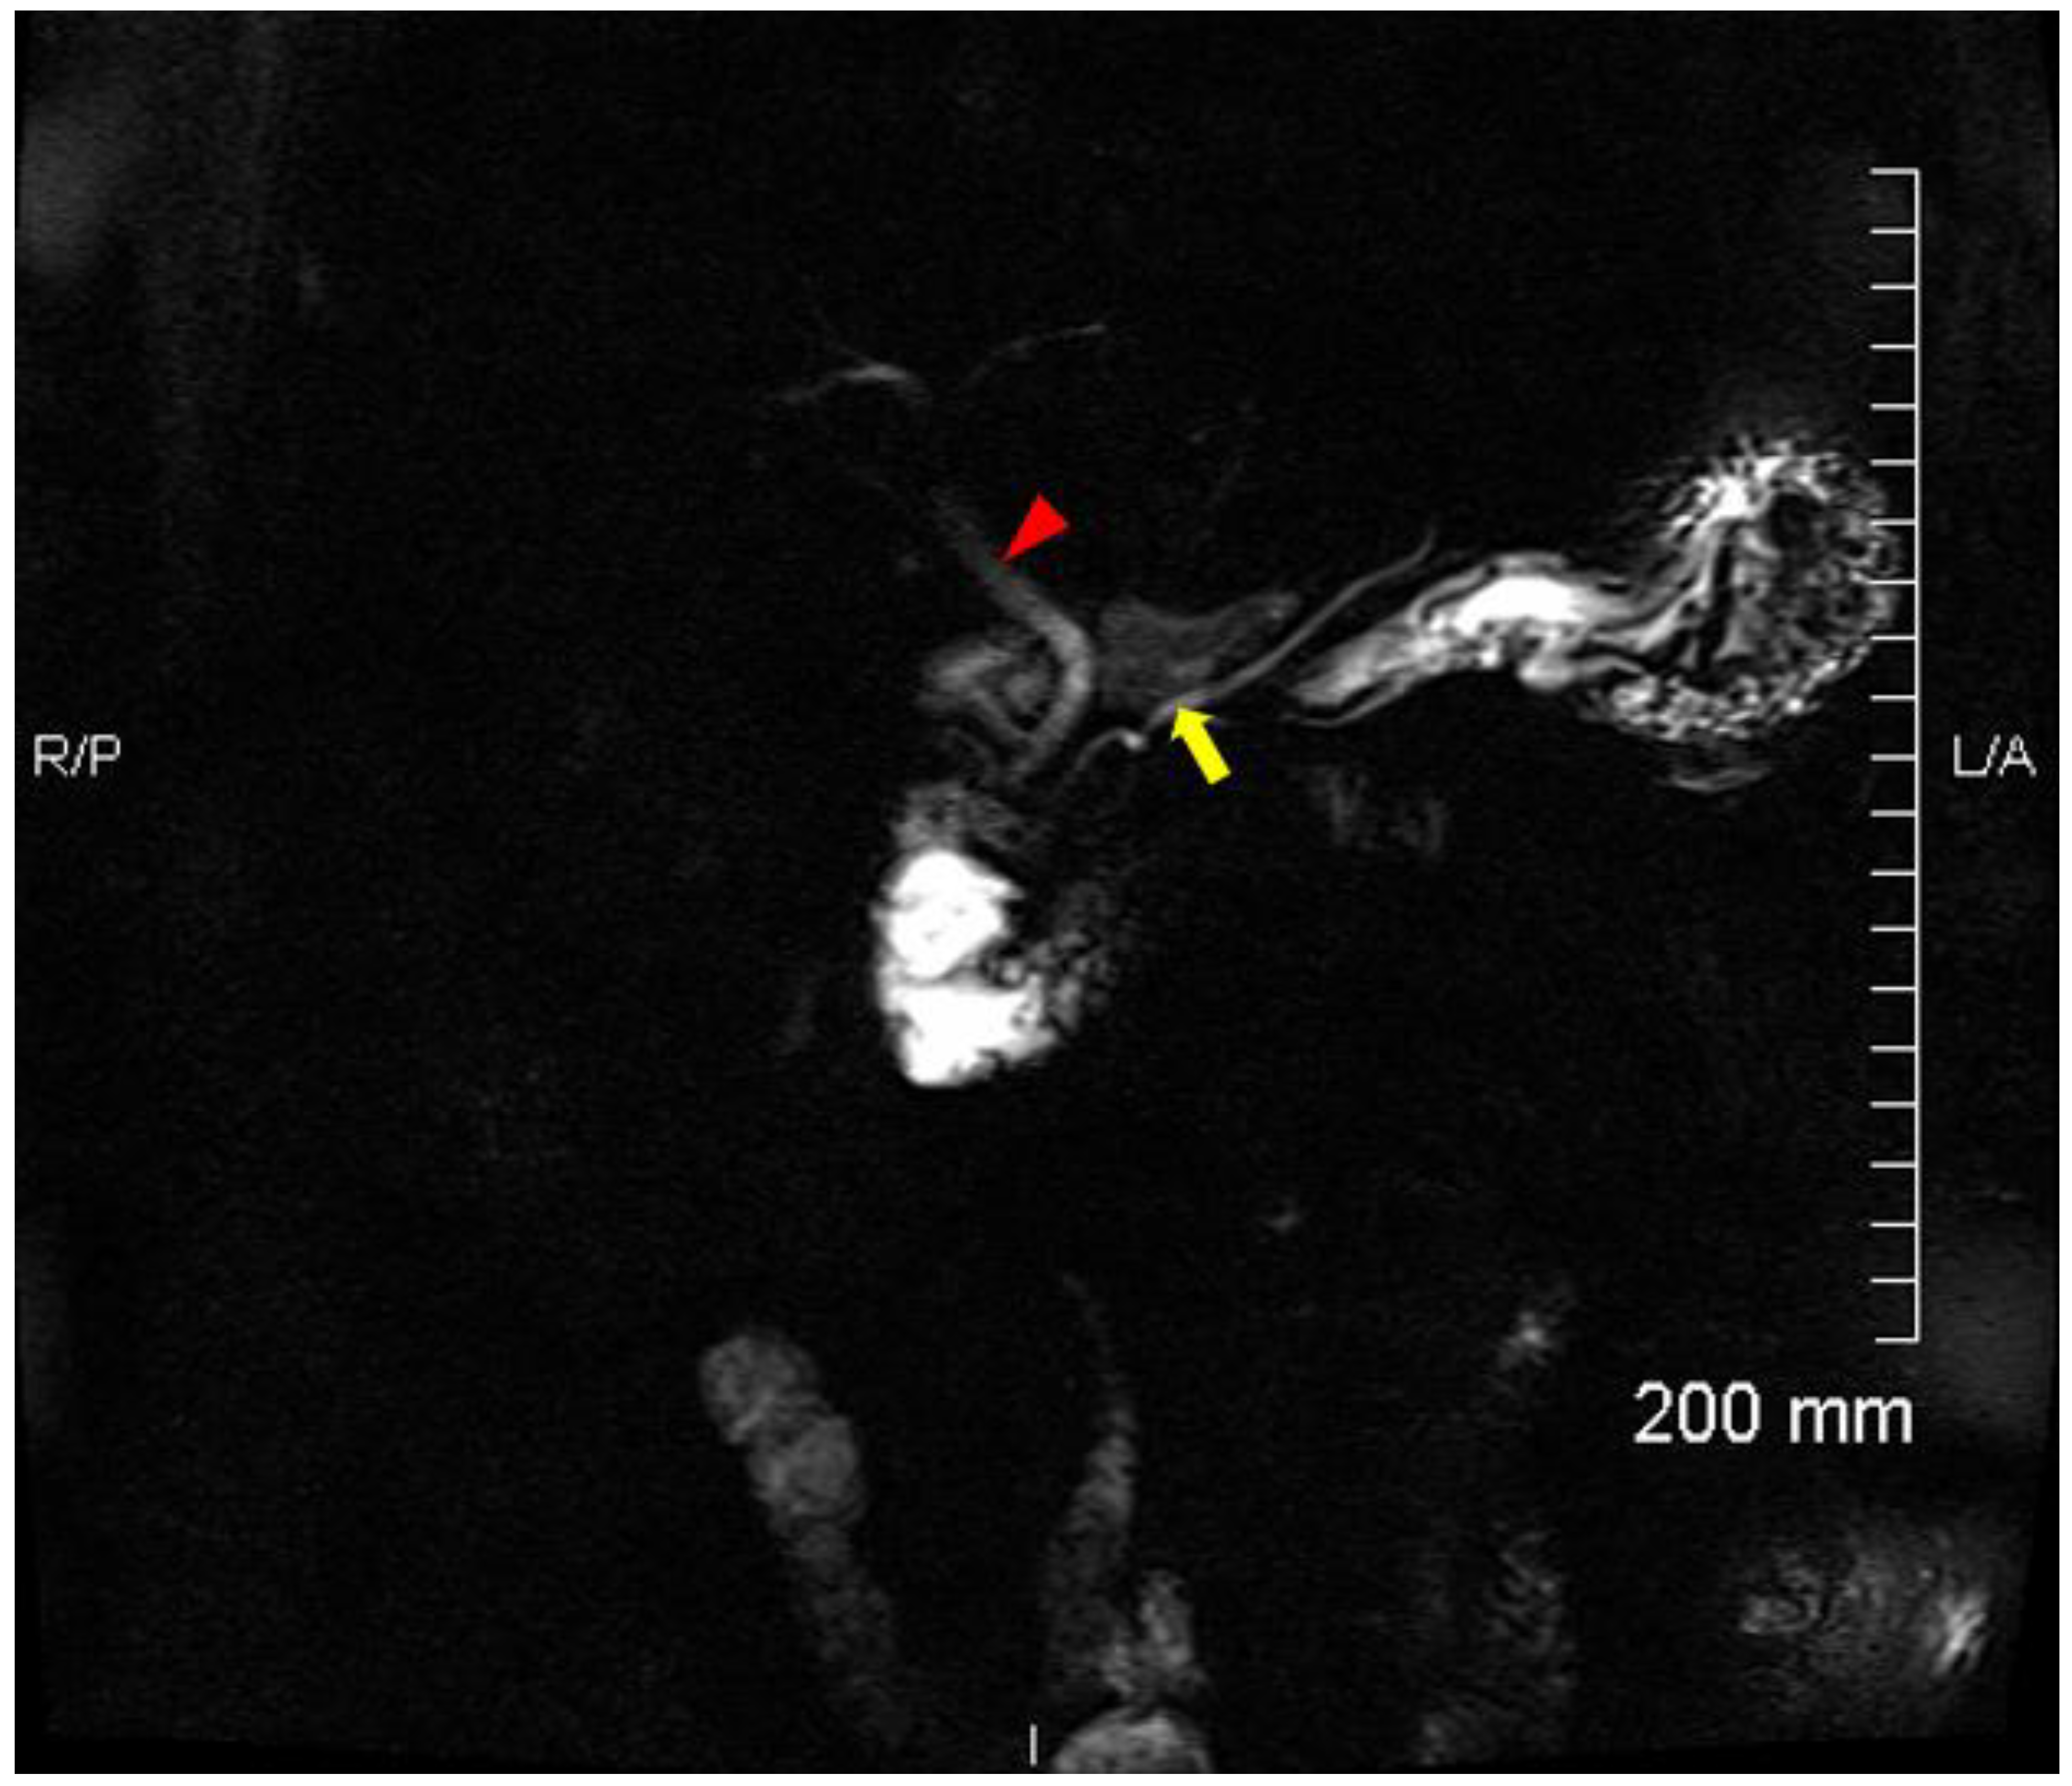

2. Case Report